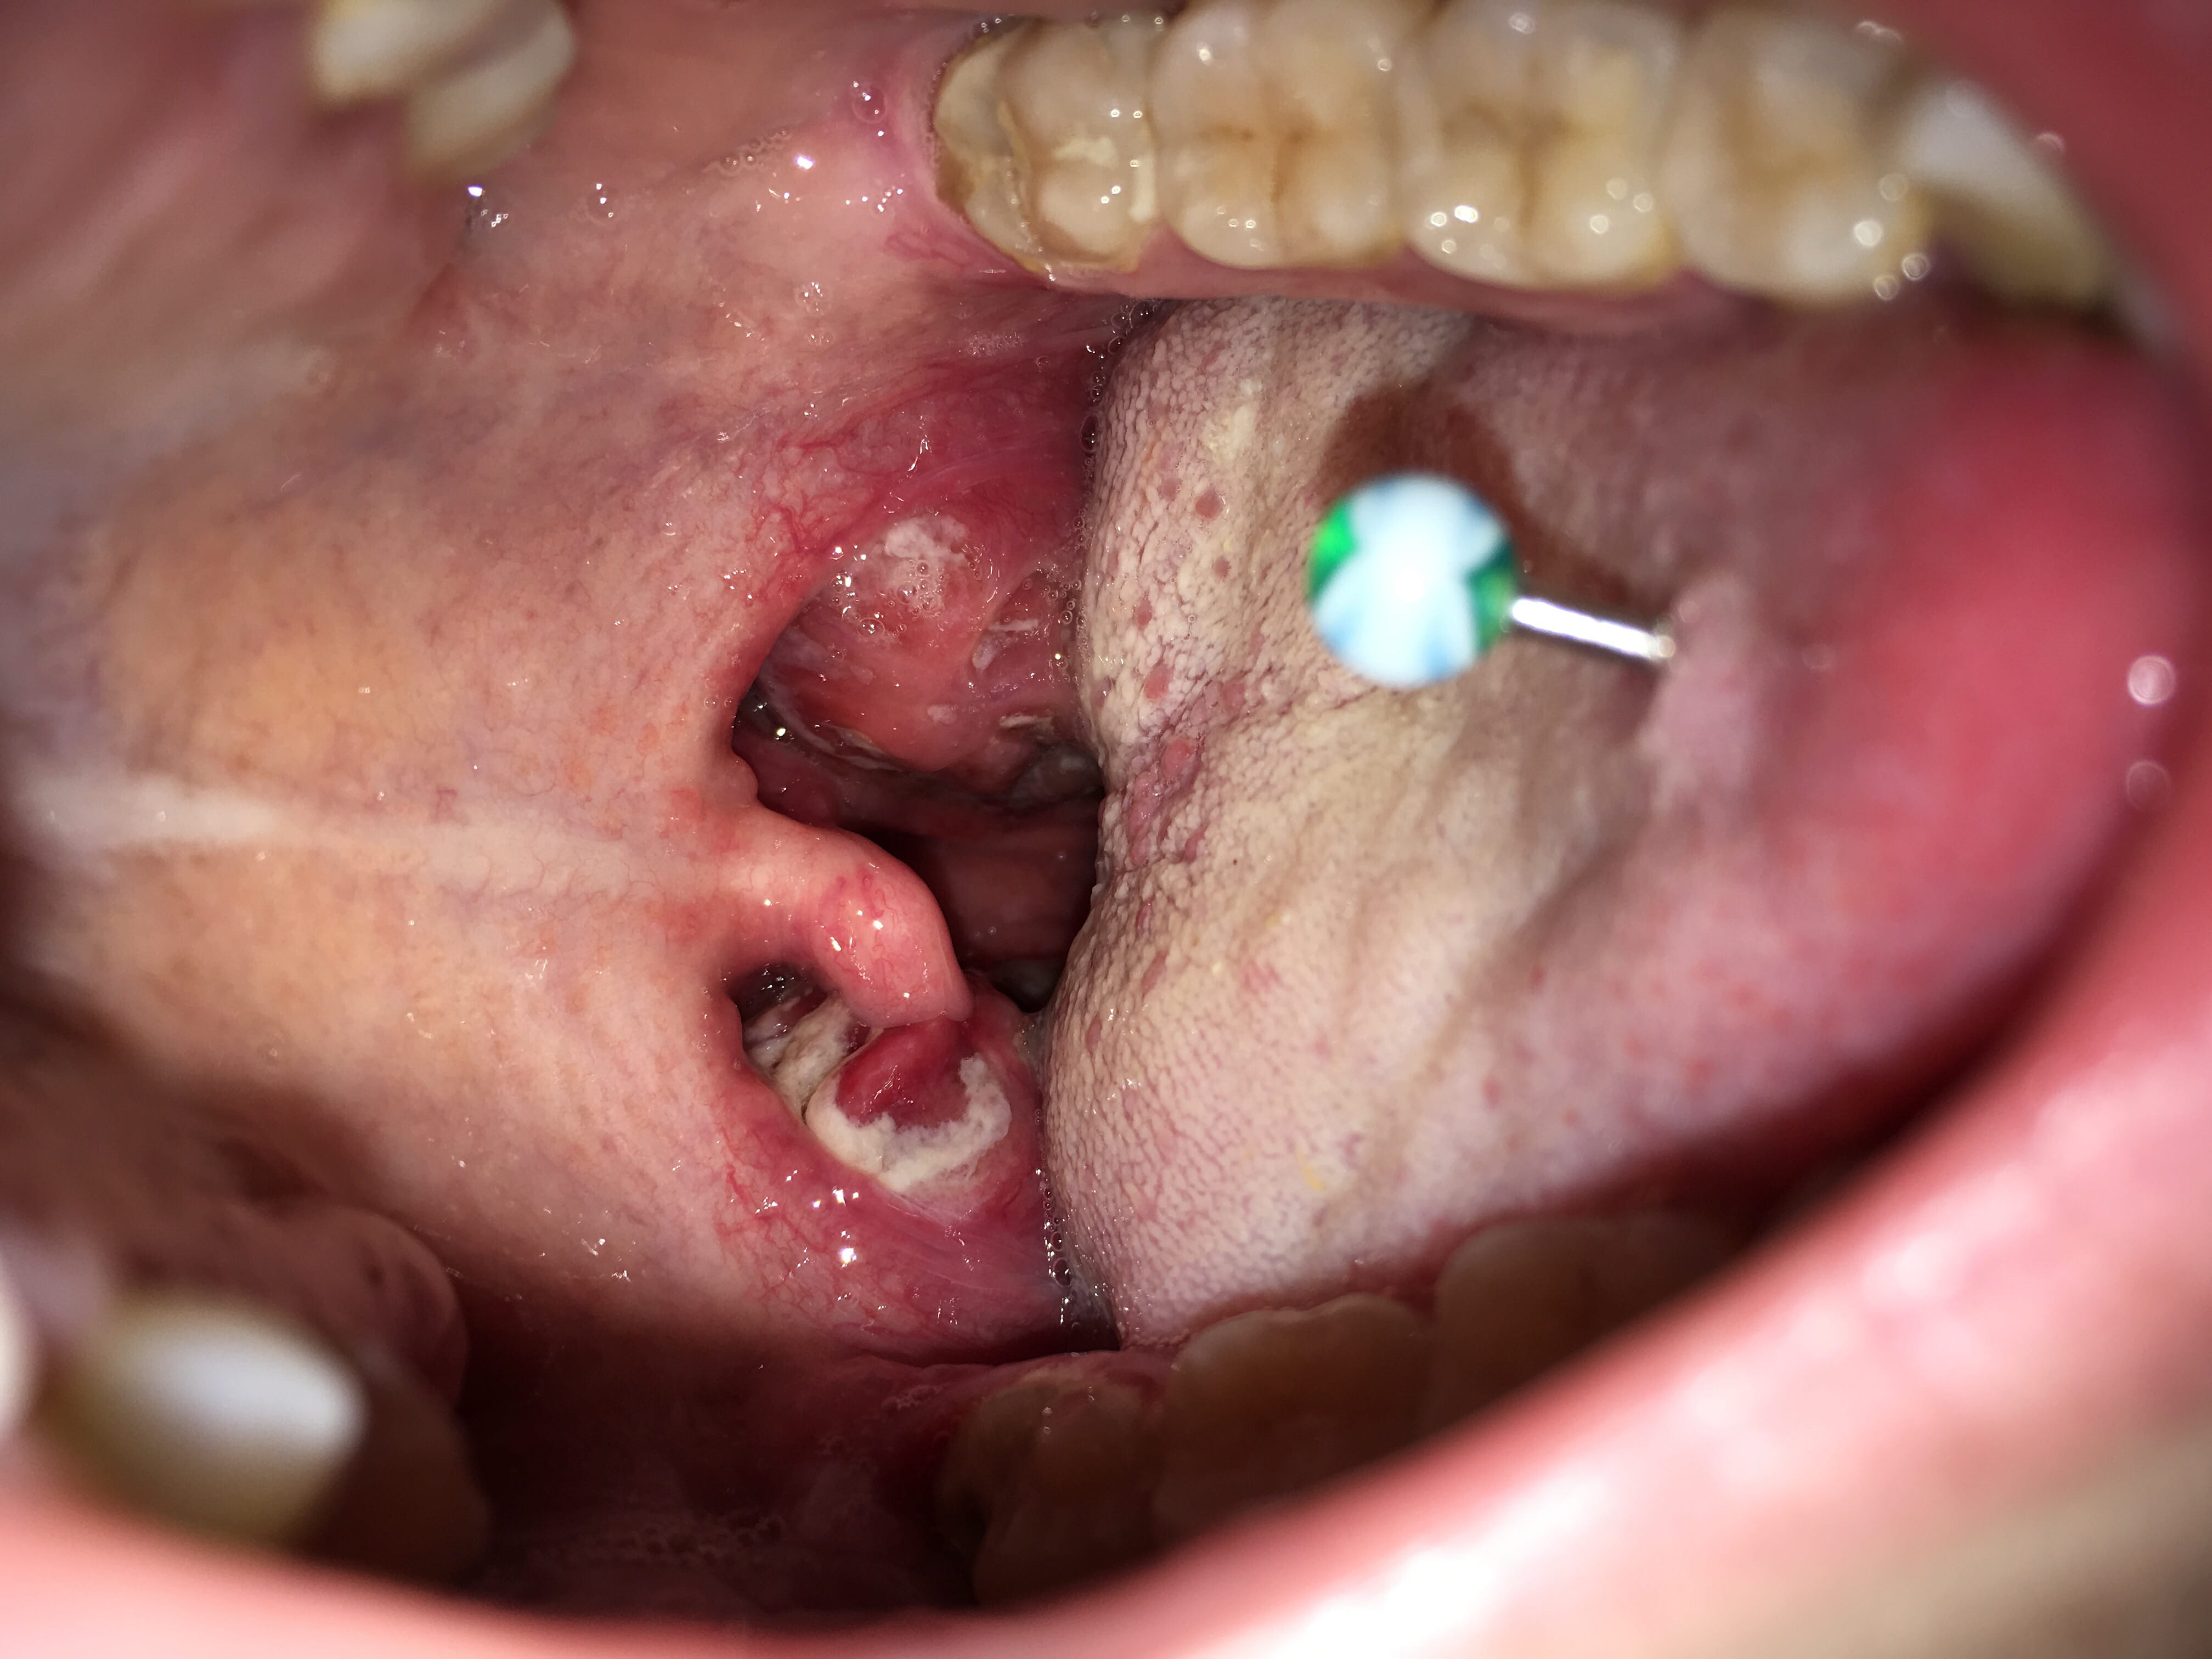

Cancer ou angine

Je m'appelle alexandrine et je vais avoir 21 ans hier matin je me suis lever avec sa a la gorge mais depuis hier et malgrer les doses importante de medicaments sa ne diminue pas les medecins pense a une angine rouge mais pas de fievre ni de toux je pers ma voix de temps a autre je me sens tres faible j'ai perdu deux killos en deux jours et je commence a cracher du sang j'avoue que j'ai tres peur car je suis maman d'un petit garcon et je suis tres sensible au moindre petit truc je n'arrive meme pas a manger je fais meme des chutes de tansion.